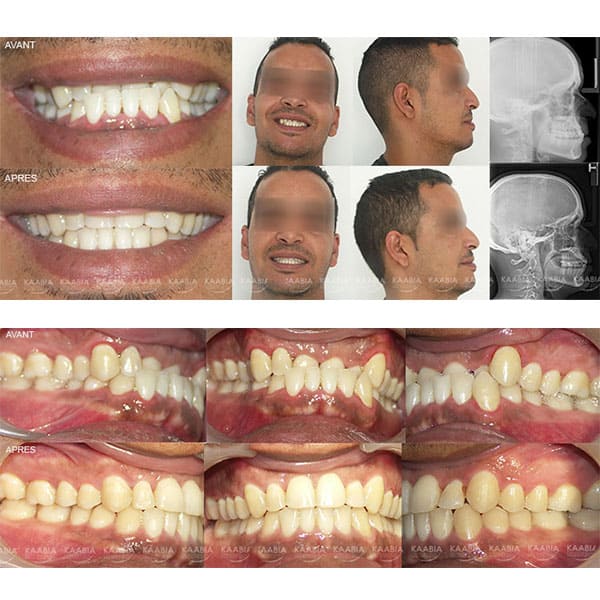

Traitement des retroalvéolies inférieurs

Cas A retroalvéolies inférieures

Cas B retroalvéolies inférieures

Cas C retroalvéolies inférieures